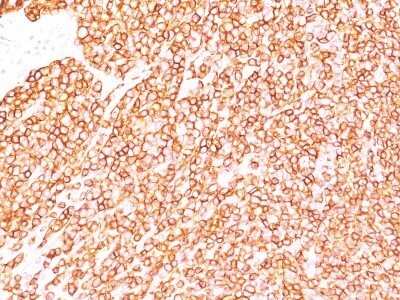

Immunohistochemistry-Paraffin: CD45RB Antibody (SPM569) - IHC-Prediluted [NBP2-44856] - Formalin-fixed, paraffin-embedded human tonsil (20X) stained with CD45RB MAb (SPM569).